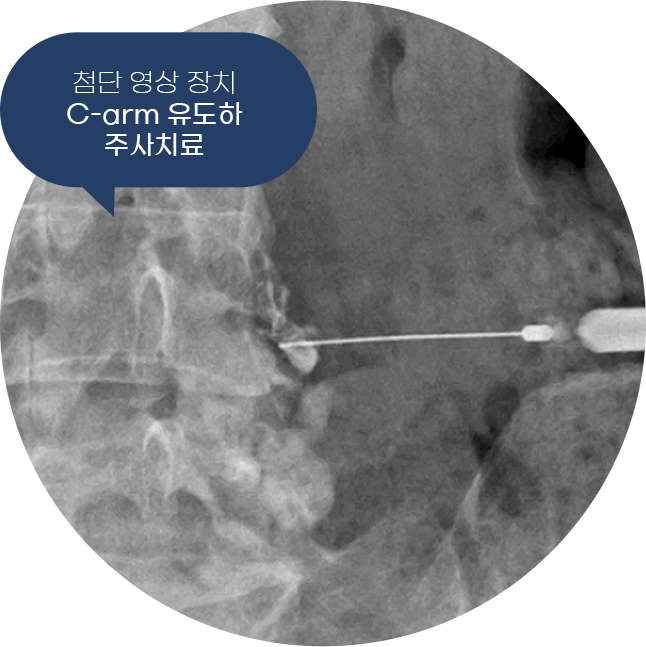

척튼튼마취통증의학과는 주사치료뿐만 아니라, 고강도 레이저 치료, 체외충격파 치료,

대상포진 치료 등 다양한 비수술 치료로 통증의 근본 원인을 치료합니다.